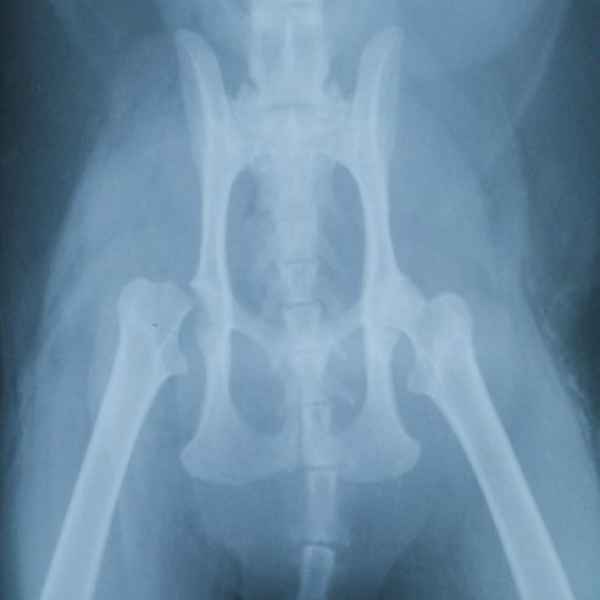

Этот пациент поступил к нам после падения с 14 этажа. На основании комплекса исследований ,была установлена полиорганная недостаточность, перелом головки бедренной кости и трех пястных костей. Прием причинял сильную боль ,ведь был перелом нижней челюсти. Нами было принято решение по установке эгофагостомы. Ежедневно проводилась инфузионная терапия и только после полной стабилизации животного была проведена хирургическая операция по восстановлению костей.